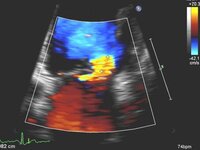

Apical 4-chamber view of 4+ (severe) mitral regurgitation and a large proximal isovelocity surface area

From the collection of Samir Kapadia and Mehdi H. Shishehbor